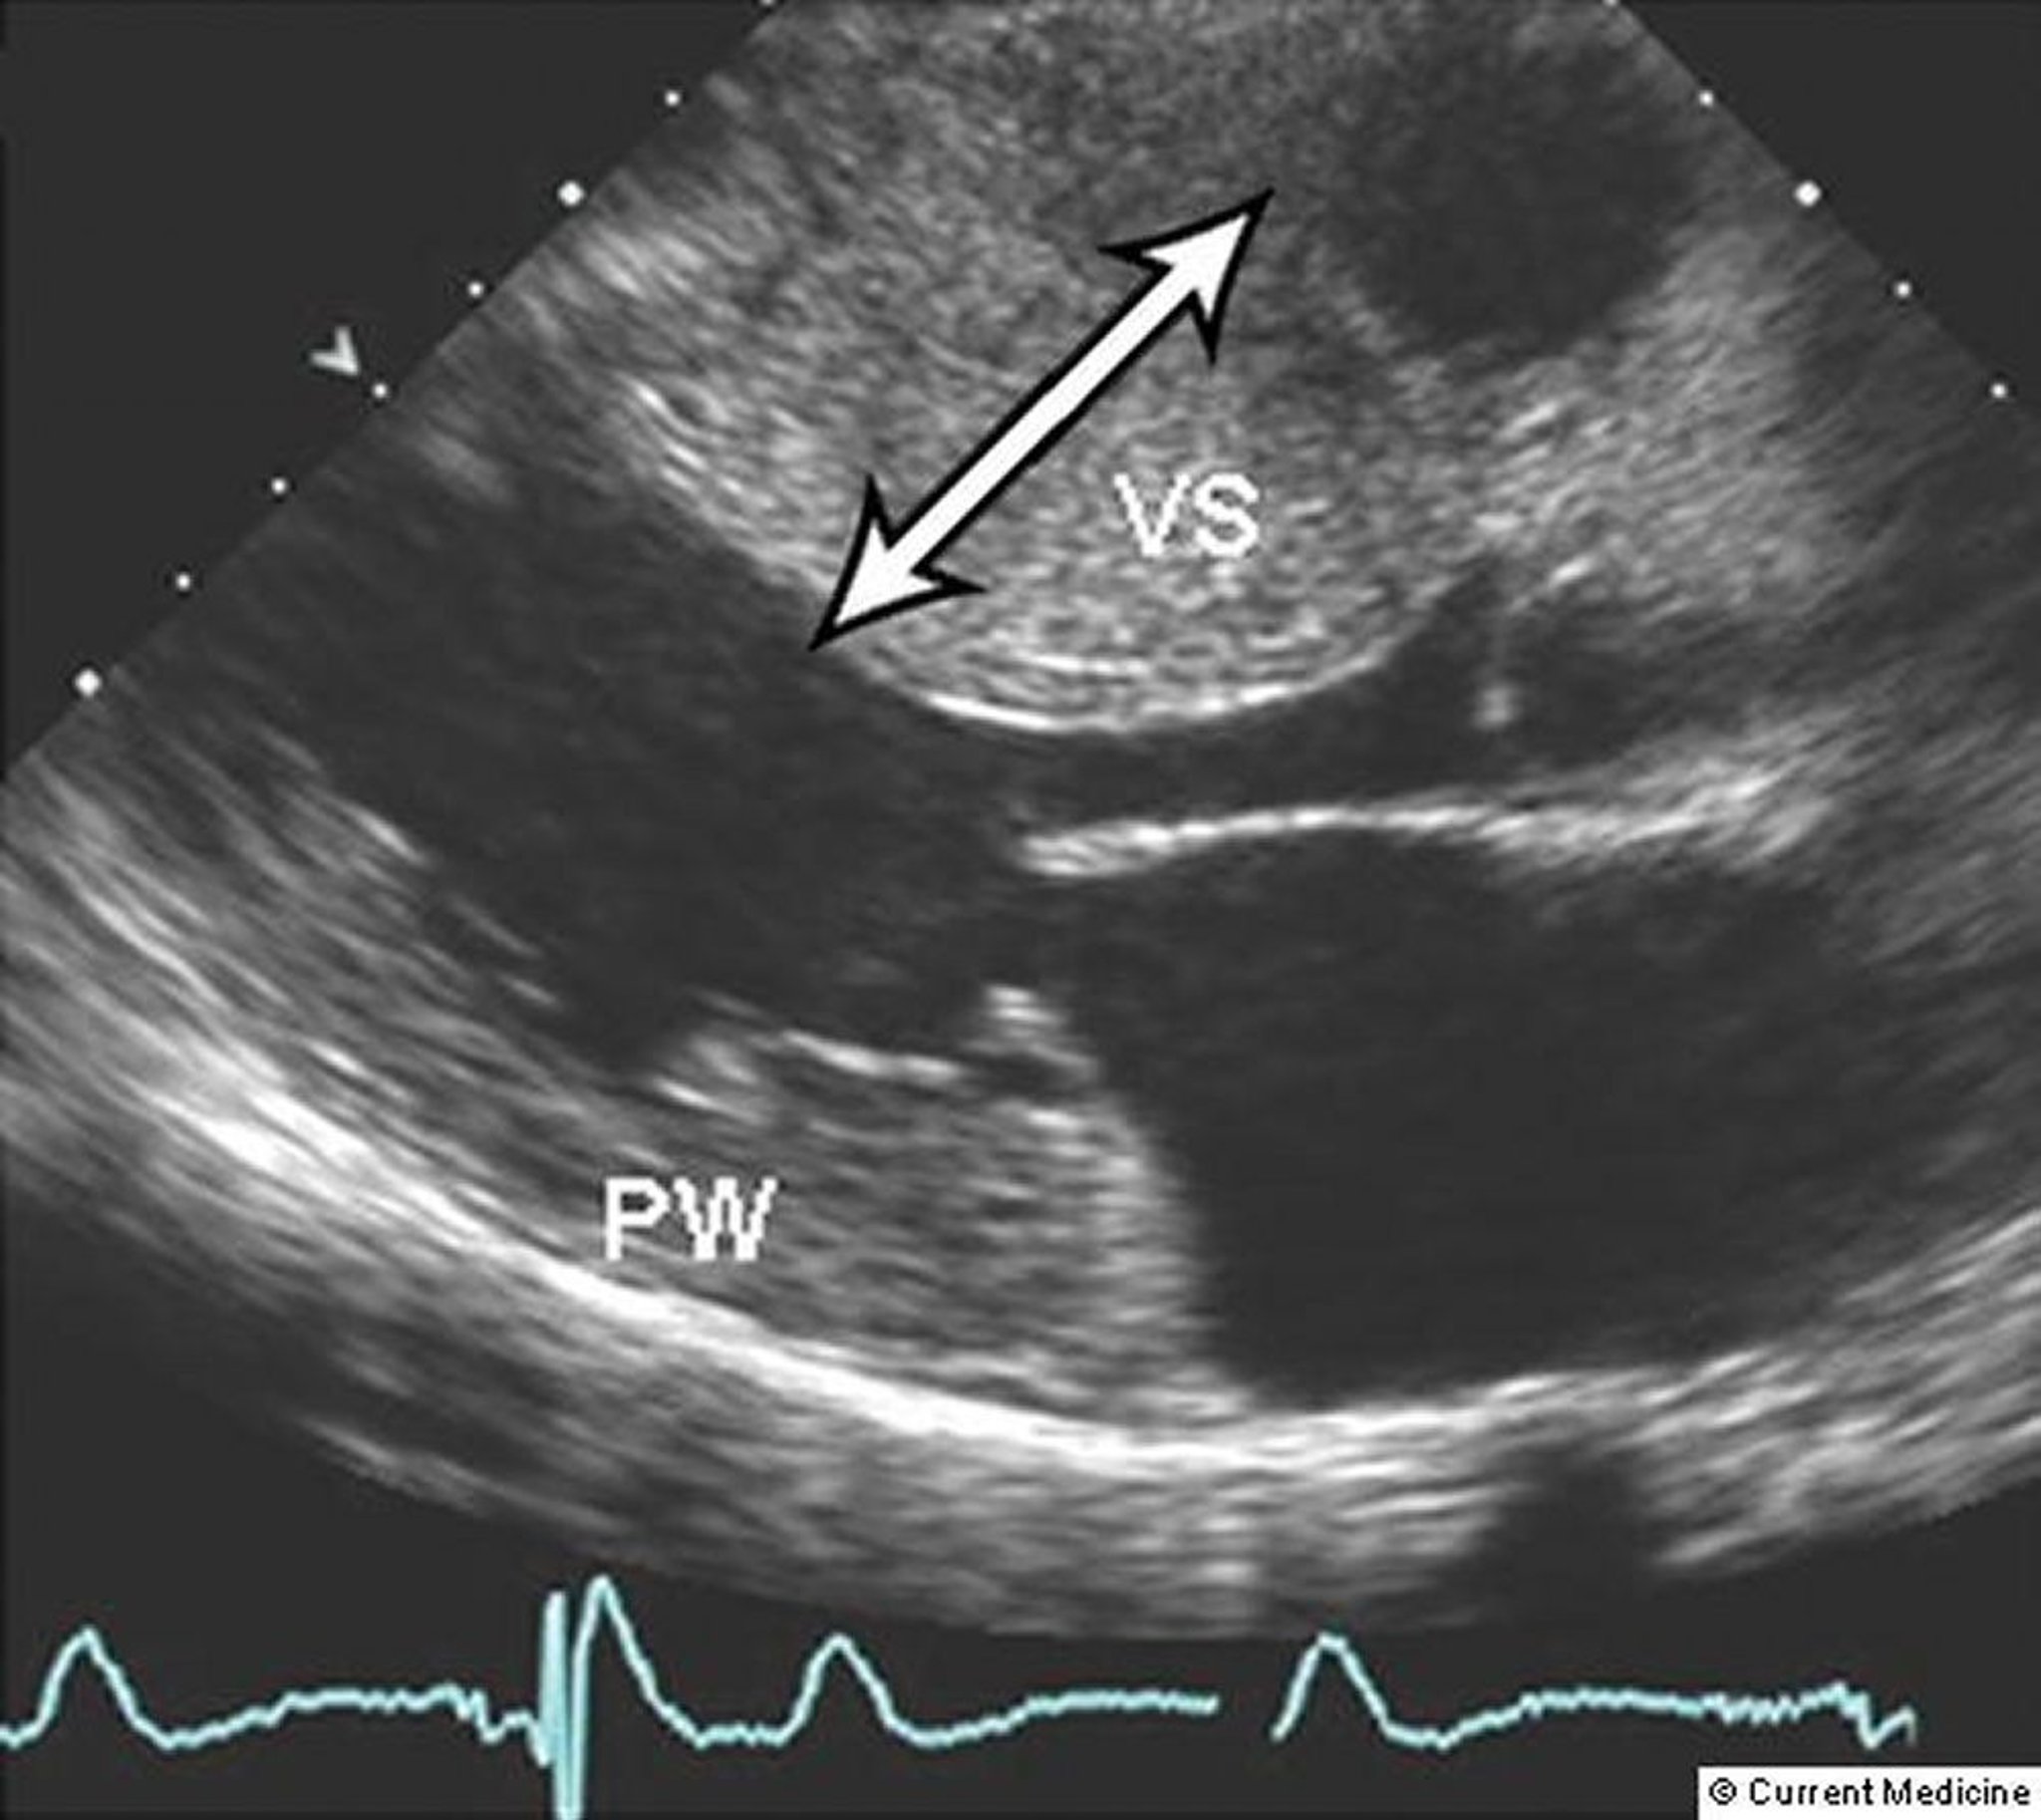

Siêu âm tim Doppler hai chiều có thể phân biệt các dạng bệnh cơ tim (xem hình ) và định lượng mức độ nặng của chứng phì đại và mức độ tắc nghẽn đường ra. Những phép đo này đặc biệt hữu ích cho việc đánh giá hiệu quả của điều trị nội khoa hoặc phẫu thuật. Van động mạch chủ đóng ở giữa thì tâm thu đôi khi xảy ra khi tắc nghẽn nặng đường ra. Nên theo dõi lưu động 24 giờ trong quá trình đánh giá ban đầu và cứ sau 1 năm đến 3 năm để đánh giá nguy cơ tử vong do tim đột ngột và giúp hướng dẫn điều trị rối loạn nhịp tim (1).

Siêu âm tim này cho thấy vách ngăn tâm thất (VS) và thành sau (PW) của tâm thất trái dày lên nghiêm trọng ở một bệnh nhân bị bệnh cơ tim phì đại.

© Springer Science+Business Media